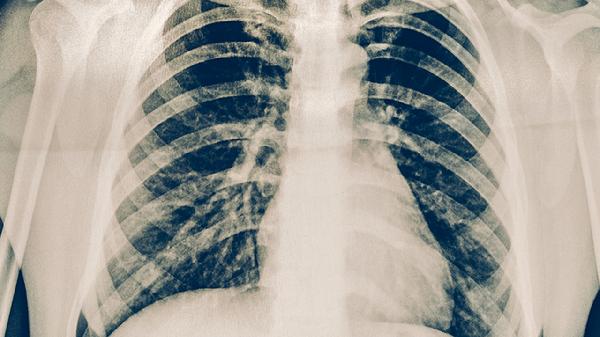

肺结核患者应保持充足营养摄入,适当补充优质蛋白和维生素以增强免疫力。治疗期间须戒酒并避免熬夜,定期复查胸部影像学和痰菌检查。出现皮肤黄染、持续恶心等症状时立即就医,由医生决定是否调整用药。严格完成全程规范化治疗是治愈结核病的关键,任何用药变更必须经过结核病专科医生的综合评估。